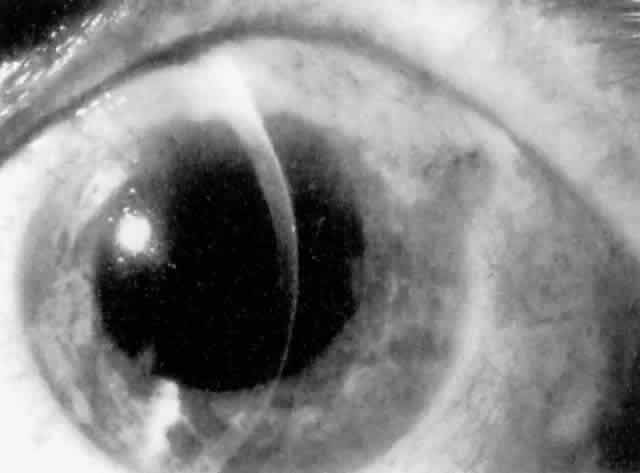

Ciliary block is also known as “malignant glaucoma” or “aqueous misdirection.” This condition results in angle closure caused by a misdirection of aqueous humor into the vitreous cavity as opposed to the posterior chamber due to resistance along the zonular-capsular-hyaloid face junction. In contrast to pupillary block, the central anterior chamber is shallow because the IOL or vitreous face is pushed forward, and a peripheral iridectomy will not prevent or resolve the acute angle closure. Ciliary block is more likely to occur in eyes with a small anterior segment and an anatomically narrow angle. Large posterior chamber IOLs (7-mm optic) in small, hyperopic eyes are also known to predispose patients to ciliary block.82

MANAGEMENT. Medical treatment consisting of cycloplegia and hyperosmotic agents is usually initiated first. Miotics are contraindicated. If the patient does not have a patent iridectomy, one should be performed to relieve any element of pupillary block. If medical management is ineffective, the posterior capsule and anterior hyaloid face should be disrupted with the Nd:YAG laser if possible (Figs. 10 and 11). If these maneuvers are not successful, pars plana vitrectomy is indicated.83,84 In a pseudophakic eye with ciliary block, IOL removal is not recommended.85

Fig. 10. Ciliary block after cataract extraction and posterior chamber lens implantation. The central chamber is shallow and the peripheral chamber flat. The intraocular lens is pushed forward, and the haptic posterior to the iris can be seen indenting the iris surface.

Fig. 11. After disruption of the posterior capsule and the anterior hyaloid face with the Nd:YAG laser, the chamber becomes immediately deep and the intraocular lens is no longer pressed against the iris. (Courtesy of Dr. E. Hodapp, Miami, FL.)